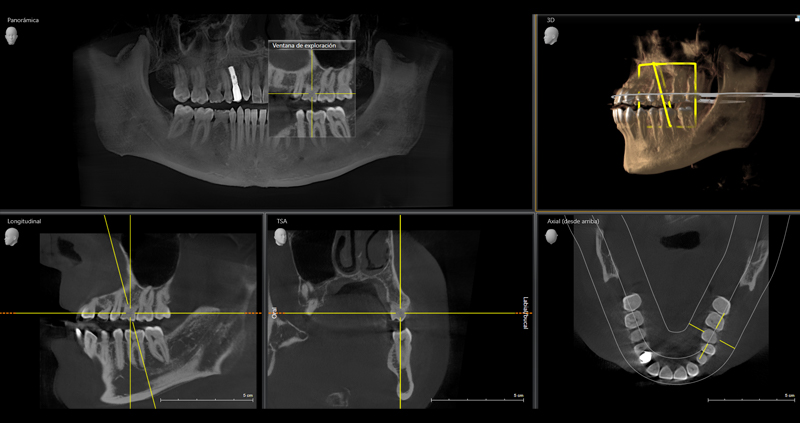

Tomografía Computarizada Cone Beam 3D

Es un examen imagenológico que se realiza para obtener un volumen en 3D de una área maxilofacial específica, tal como un Scanner médico, pero con menor radiación.

En cambio con el Cone Beam se obtiene un modelo tridimensional (3D) que el profesional puede manipular mediante un software especial, para ver estructuras por capas, realizar mediciones, ver tejidos duros, tejidos blandos y lesiones.

Ya que con la Tomografía Computarizada se obtiene una repsentación en volumen de las estructuras maxilofaciales, es te examen resulta útil para:

• Planificar cirugías de implantes.

• Localizar origen de un dolor.

• Diagnosticar trastornos temporomandibulares

• Detectar, medir y tratar tumores.

• Evaluar piezas dentarias, senos paranasales, articulaciones, canales nerviosos y entre otras estructuras.